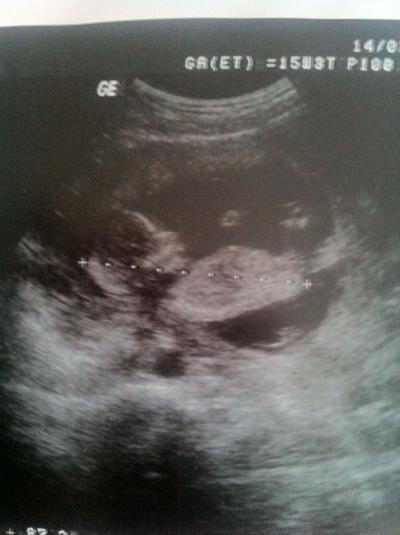

Hallöchen, hatte ja versprochen, den besonderen Valentinsgruß von meinem Mini Euch zu zeigen... hier ist es... Vielleicht können auch die anderen Mädels mit Fa von gestern ihr Bildi reinstellen, würde mich freuen... LG Mone Wünsche Euch allen einen schönen Mittwoch...

Bild zu Versprochenes Bildchen von gestern... - Forum für August - Mamis